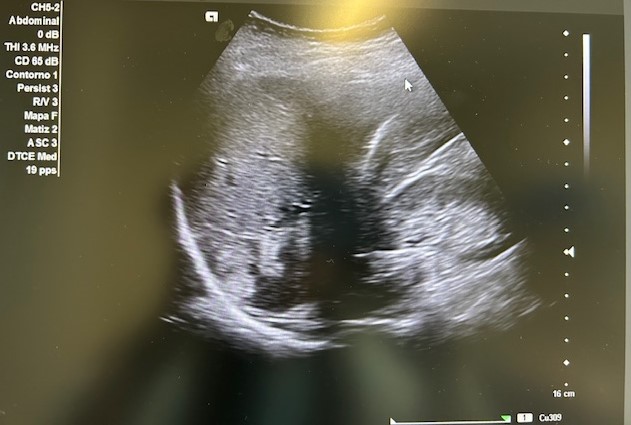

En la ecografía podemos apreciar hepatomegalia > 16 cm con múltiples imágenes en su interior hiperecogénicas sugestivas de LOE. No otros hallazgos a destacar.

El paciente fue valorado en Consultas Externas confirmando el diagnóstico. Se realiza ecografía abdominal con hallazgos de múltiples nódulos hepáticos de entre 12-35mm. En la colonoscopia, neoplasia circunferencial con aumento de consistencia, áreas ulceradas y necrosis, con estenosis incompleta, siendo compatible con adenocarcinoma de sigma.